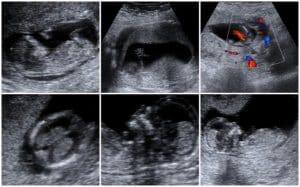

Second and third trimester ultrasound

During the second and third trimester, ultrasonography is used to measure fetal biometry to determine growth and detect anatomic abnormalities; biparietal diameter, abdominal circumference, fetal presentation, and amniotic fluid volume.

Fetal anomalies are best detected by a detailed anatomic scan which should be done between 18 and 20 weeks of gestation. Targeted scans can be done at any point, however standard fetal anomaly scans occur at 11 to 13 weeks, and fetal growth scans are usually performed at 20 to 24 weeks and later at approximately 3 to 4 weeks intervals.

Second trimester sonogram